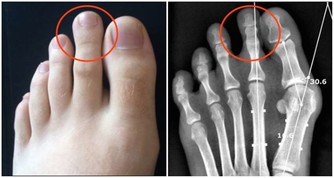

除此之外,常見的還有痛風、肥胖、風濕性關節炎以及類風濕性關節炎等都會引起“膝蓋”疼,由此可見,我們需要對此引起高度的重視,做到“早發現,早治療”,防止由於個人忽視導致疾病逐漸加重、惡化,進而對家庭和日常生活產生不良影響。